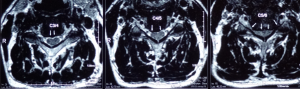

The most common cervical joints that are compressed on the cervical intervertebral disc are the fifth and sixth cervical vertebrae (C5, 6). Generally, X-rays show that the space between the vertebrae is reduced and the vertebrae have signs of degeneration. In addition to the fifth and sixth cervical vertebrae, there are also third and fourth cervical vertebrae (C3, 4), which are also parts of greater compression, and the changes in other vertebrae will follow.

The pain and paralysis of each cervical disc herniation can be distributed in different area of the hand (Figure 1). To distinguish where the intervertebral disc is herniated, it is necessary to check the arm muscle strength in, perform reflex nerve tests, and notice with the patient’s symptoms in order to confirm the diagnosis. Surgery cannot be made solely on the report of magnetic resonance (MRI). Magnetic resonance is to help doctors to confirm the diagnosis, not to help doctors diagnose the disease.